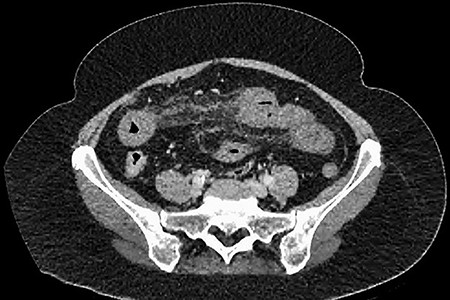

A 61-year-old female presented to a regional hospital with a 3-week history of intermittent diarrhoea, vomiting and generalized abdominal pain. She had a diffusely tender abdomen but was not peritonitic, and was shocked with a heart rate of 110 beats per minute, blood pressure of 89/45 mmHg and was peripherally cool. Her blood tests revealed a lactate of 7.2 mmol/L, which worsened to 7.8 mmol/L during resuscitation with intravenous fluids, and white cell count was 30.9 × 109/L, with an international normalized ratio (INR) of 1.4. She had an acute kidney injury with a creatinine of 119μmol/L and estimated glomerular filtration rate (eGFR) of 43 mL/min/1.73m2. Computed tomography (CT) revealed extensive thickened loops of non-enhancing small bowel with pneumatosis, moderate free fluid and a large splenic infarction. There was extensive thrombosis of the splenic vein and superior mesenteric vein extending into the portal vein to the level of the porta hepatis. Her background history included factor V Leiden and protein S deficiency, for which she had been non-compliant with warfarin during this illness. She had no surgical history (Figs. 1–5).

CT showing multiple thick-walled, non-enhancing loops of small bowel.